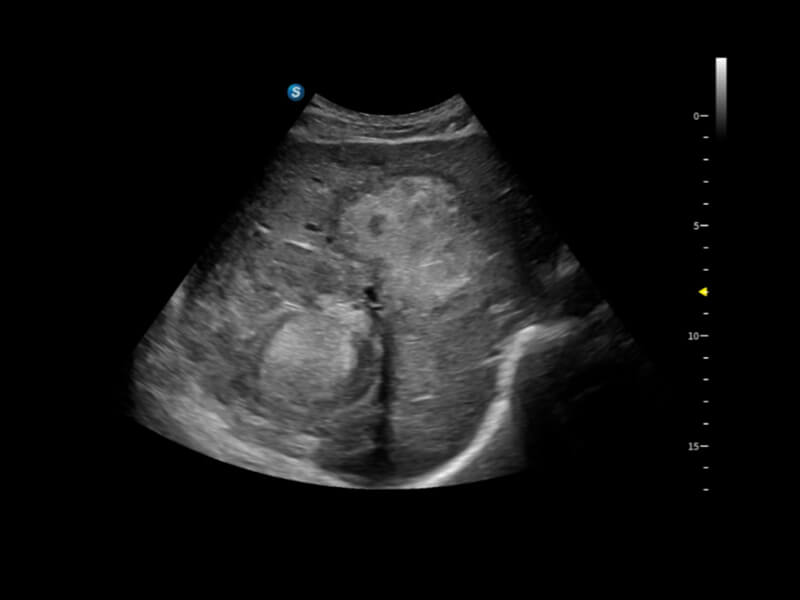

作為開立醫(yī)療全新打造的超高端旗艦超聲產(chǎn)品,從探頭抬起喚醒開啟掃查到多維探頭發(fā)射接收,通過先進(jìn)的場(chǎng)成像發(fā)射、自適應(yīng)聚合重建等技術(shù),基于RF Data原始射頻數(shù)據(jù)在圖像生成、高端功能等方面實(shí)現(xiàn)突破,提供多科室綜合臨床解決方案。

S80 提供多樣化超聲成像技術(shù),可滿足不同科室的需求,在助力掃查診斷和介入治療中發(fā)揮著重要作用。